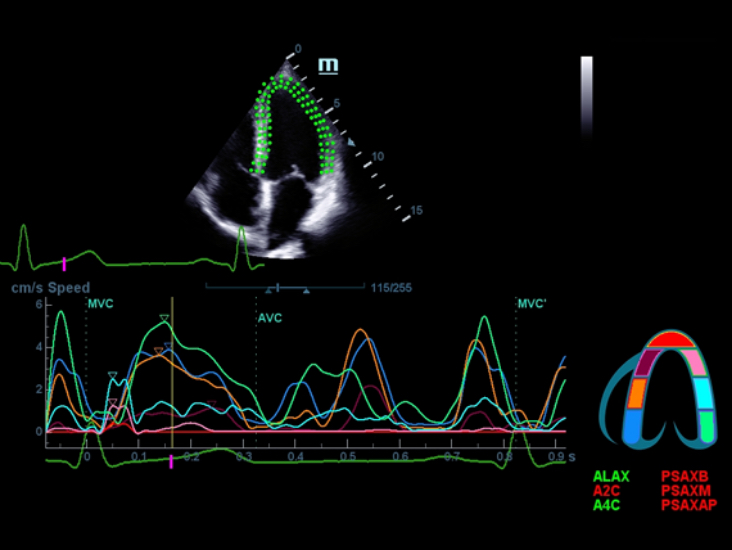

X-Insight adalah solusi untuk visualisasi lebih lanjut.

Sebagai mitra yang menyeluruh, DC-60 Exp dengan X-Insight memfokuskan dirinya untuk menghadirkan solusi yang komprehensif untuk membantu Anda mengelola semua aspek praktik klinis harian dengan mudah dan baik.

Dengan pemahaman mendalam atas kebutuhan pelanggan, DC-60 Exp dengan X-Insight dirancang untuk menyajikan efisiensi tinggi dengan pencitraan yang presisi, yang didukung oleh eXpress Clarity, eXceptional Intelligence, dan eXceeding Experience.